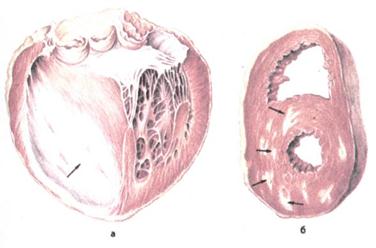

Рис. 33. Хроническая ишемическая болезнь сердца

а — постинфарктный крупноочаговый кардиосклероз (показано стрелкой);

б — рассеянный очаговый кардиосклероз (рубцы показаны стрелками).